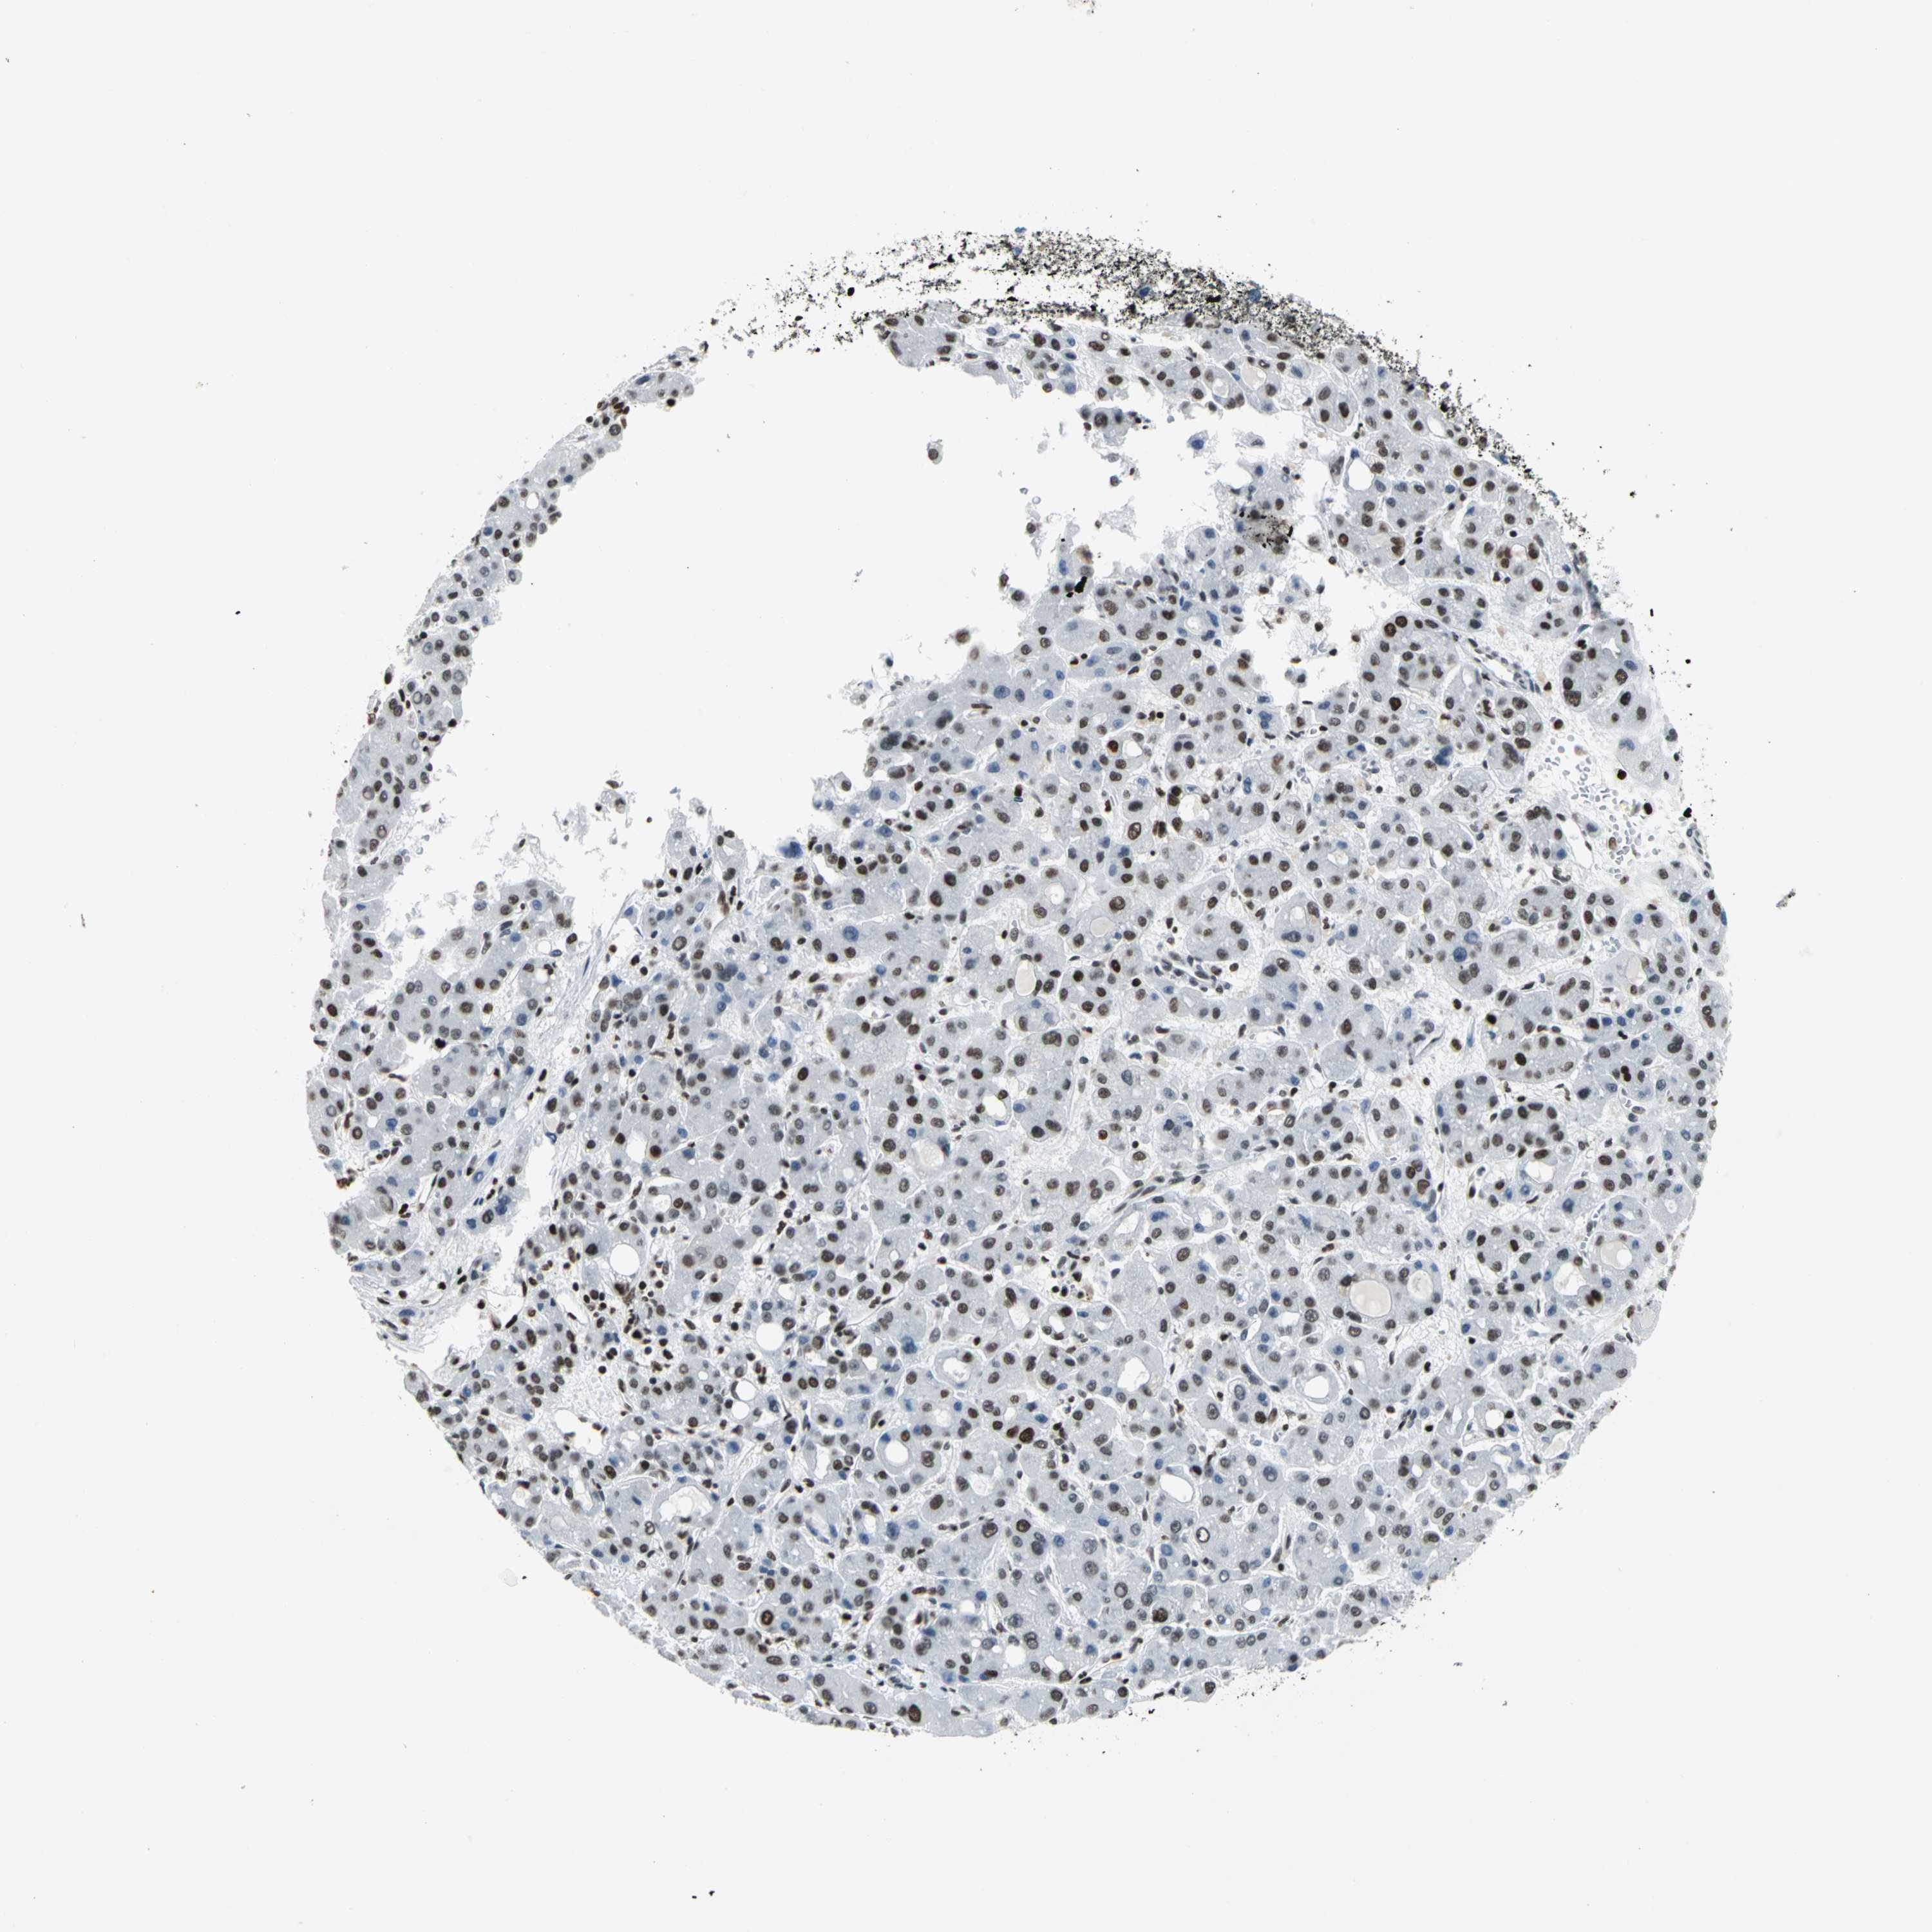

LIVER CANCER - Protein expressioni

A mouse-over function shows sample information and annotation data. Click on an image to view it in a full screen mode. Samples can be filtered based on level of antibody staining by selecting one or several of the following categories: high, medium, low and not detected. The assay and annotation is described here.

Note that samples used for immunohistochemistry by the Human Protein Atlas do not correspond to samples in the TCGA dataset.

Antibody stainingi

Antibody staining in the annotated cell types in the current human tissue is reported as not detected, low, medium, or high, based on conventional immunohistochemistry profiling in selected tissues. This score is based on the combination of the staining intensity and fraction of stained cells.

Each image is clickable and will lead to virtual microscopy that enables deeper exploration of all samples and also displays staining intensity scores, fraction scores and subcellular localization as well as patient and tissue information for each sample.

Antibody HPA004911

Staining

High

Medium

Low

Not detected

Intensity

Strong

Moderate

Weak

Negative

Quantity

>75%

75%-25%

<25%

None

Location

Nuclear

Cytoplasmic/membranous

Cytoplasmic/membranous,nuclear

Cholangiocarcinoma

Carcinoma, Hepatocellular, NOS